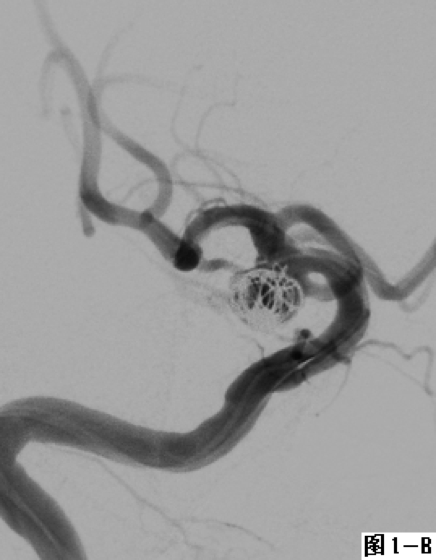

图1 采用经典式双微导管技术栓塞右侧后交通不规则形态动脉瘤。A.DSA显示右侧后交通动脉“葫芦形”不规则动脉瘤;B.在合适的工作角度下降2根微导管置入瘤体内不同位置;C.通过2根微导管交替填塞微弹簧圈,至填塞致密。